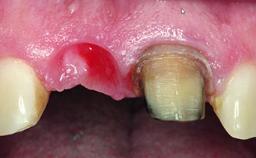

Replacement of a Failing Upper Left Central Incisor: Immediate Placement of an RC Bone Level Implant and Provisionalization

A healthy 23-year-old female patient was referred for a consultation on replacing tooth 21 with an implant-supported restoration. The patient had recently moved to the area and reported a history of endodontic and periodontal treatment for tooth 21. The tooth had been deemed non-restorable by her previous periodontist but since she was going to be moving, he recommended consulting to a dentist in her new city to continue her treatment. A review of her medical history yielded no significant findings and no known drug allergies. The analysis of her smile revealed a medium to high symmetrical smile line and a slightly discolored tooth 21.

Socket Integrity Damage to one or more bone walls

Bone Volume Damage to one or more socket walls